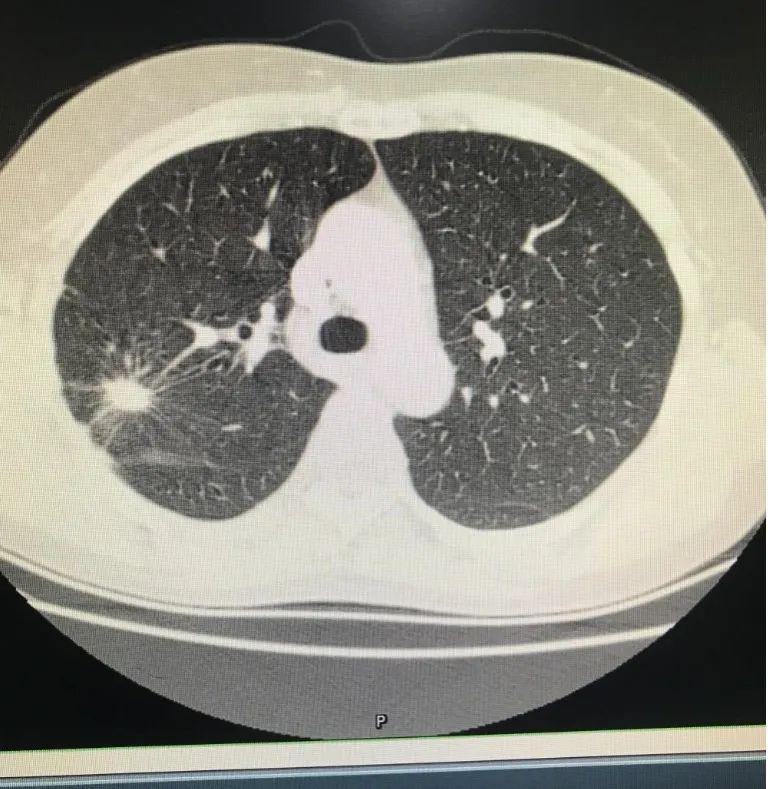

近日,患者洪某因發(fā)熱咳嗽在其他醫(yī)院治療多日未有改善而慕名來到江西省胸科醫(yī)院,腫瘤科副主任醫(yī)師陳軒接診后,復(fù)查CT影像示右上肺1.8x1.0cm結(jié)節(jié)的占位性改變病灶。經(jīng)與主任醫(yī)師李真斌確認(rèn),當(dāng)即安排次日加班行經(jīng)皮肺穿。

經(jīng)皮肺穿是在檢查出有肺部病灶的情況下,通過x線透視下定位或B超指導(dǎo),或在ct指導(dǎo)下,用穿刺針刺入病灶部位,抽取部分病變組織,再將這些病變的細(xì)胞或組織進(jìn)行病理學(xué)檢查以明確診斷(判斷是病毒性感染、炎癥、還是良性或惡性腫瘤等)。

由于該患者肺功能差,呼吸幅度大,病灶小,血供較豐富,所在位置被肩胛骨擋住,這無疑大大增加了穿刺的難度,是對(duì)醫(yī)生穿刺技術(shù)和經(jīng)驗(yàn)的一次大考驗(yàn)。李主任和陳軒仔細(xì)閱片,精心設(shè)計(jì)穿刺途徑,消除患者緊張情緒。患者積極配合,取好體位后,定位穿刺一針到位,精準(zhǔn)活檢,取材滿意,患者無氣胸?zé)o咯血,術(shù)后精神狀態(tài)良好。